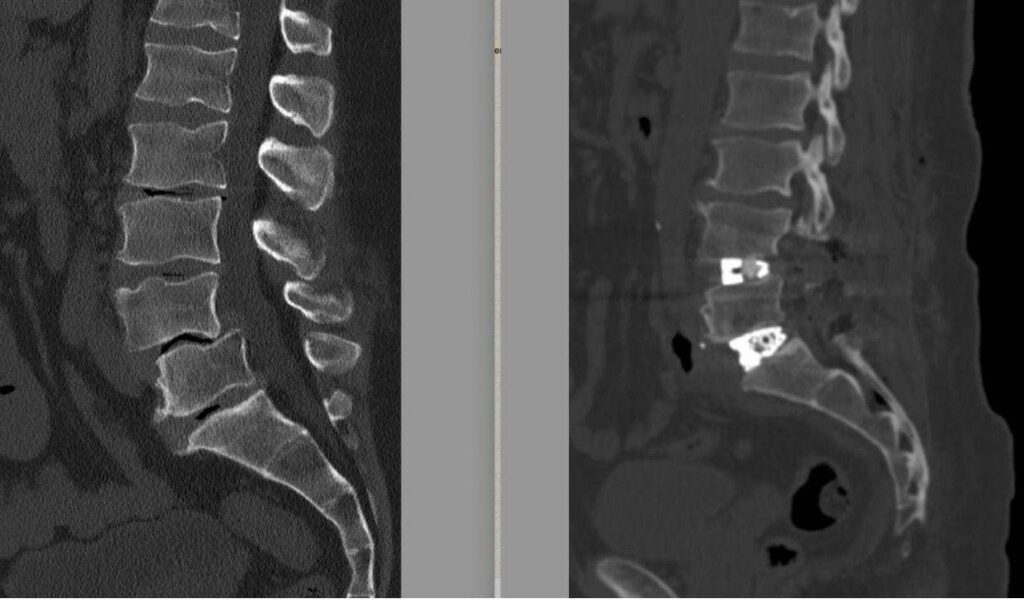

À l’hôpital de Tibériade à Rome, établissement de soins et de recherche GVM accrédité auprès du Service national de santé, « une opération de chirurgie de la colonne vertébrale très complexe a été réalisée avec succès sur un patient de 55 ans souffrant de spondylolisthésis L4-L5 et de discopathie sévère L5-S1, associée à un grave déséquilibre de l’équilibre sagittal de la colonne vertébrale, en utilisant la technique Alif (Anterior Lumbar Interbody Fusion – arthrodèse intersomatique avec approche combinée antérieure et postérieure) sur les deux niveaux. Une technique encore peu répandue en Italie, qui nécessite des compétences élevées, mais qui permet une récupération fonctionnelle plus rapide », décrit une note. « La structure romaine – lit-on – est un point de référence pour la chirurgie complexe de la colonne vertébrale et parmi les rares centres en Italie à pratiquer la technique Alif ; cette opération confirme le parcours de développement de l’hôpital de Tibériade comme référence dans le domaine de la chirurgie très complexe ».

Le diagnostic était un spondylolisthésis entre la quatrième et la cinquième vertèbre lombaire (L4-L5), pathologie dégénérative chronique caractérisée par le glissement progressif d’une vertèbre sur l’autre, associée à une discopathie du disque intervertébral L5-S1. Au fil du temps – soulignent les experts – cette déformation a entraîné une compression importante des racines nerveuses, provoquant une sciatique bilatérale invalidante, avec des douleurs irradiant vers les membres inférieurs qui se sont aggravées en position debout et pendant les activités quotidiennes et professionnelles, compromettant considérablement la qualité de vie.

Une étape fondamentale dans la planification de l’intervention chirurgicale – explique la note – a été l’étude des « paramètres spino-pelviens », réalisée sur une radiographie de toute la colonne vertébrale. Ceux-ci aident le chirurgien de la colonne vertébrale à choisir l’approche chirurgicale la plus correcte et le type d’implants à utiliser en fonction du degré de lordose à restaurer. « Aujourd’hui, la chirurgie de la colonne vertébrale ne se limite pas à libérer les nerfs ou à stabiliser un segment considéré comme instable – précise le neurochirurgien et chirurgien de la colonne vertébrale – mais vise à reconstruire une structure posturale la plus physiologique possible. Le non-respect et, si possible, la restauration de ces paramètres peuvent conduire, avec le temps, à l’échec de la construction implantée dans la colonne vertébrale ou à la dégénérescence prématurée des segments de la colonne adjacents à celui traité ».

L’opération a été réalisée début février 2026 et a duré environ 6 heures, rapportent les médecins. 12 heures après l’intervention, un scanner abdominal a été réalisé sans produit de contraste pour exclure toute complication liée à l’abord antérieur, tandis qu’une radiographie verticale a permis de vérifier immédiatement la qualité de la correction obtenue. Le déroulement postopératoire s’est déroulé sans incident. Le patient s’est réveillé avec une amélioration substantielle des symptômes de la sciatique et avec des douleurs limitées aux plaies chirurgicales, gérables avec des analgésiques courants. En l’absence de complications neurologiques ou générales, il est sorti au deuxième jour postopératoire. Une fois de retour chez lui, le patient poursuit le suivi clinique avec l’équipe de chirurgie de la colonne vertébrale de l’hôpital de Tibériade. Dans les premières semaines, la rééducation consiste principalement à marcher et à reprendre progressivement les activités quotidiennes sans solliciter la colonne vertébrale.